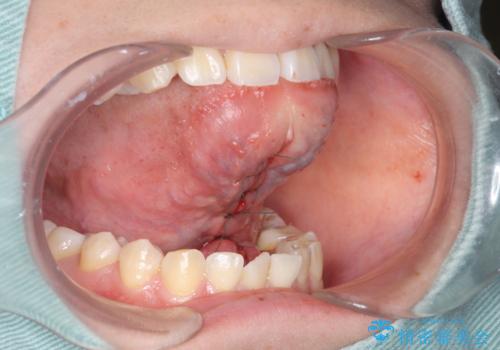

舌の可動範囲が広がり満足していただけました。

舌小帯切除は当日行う事ができます。